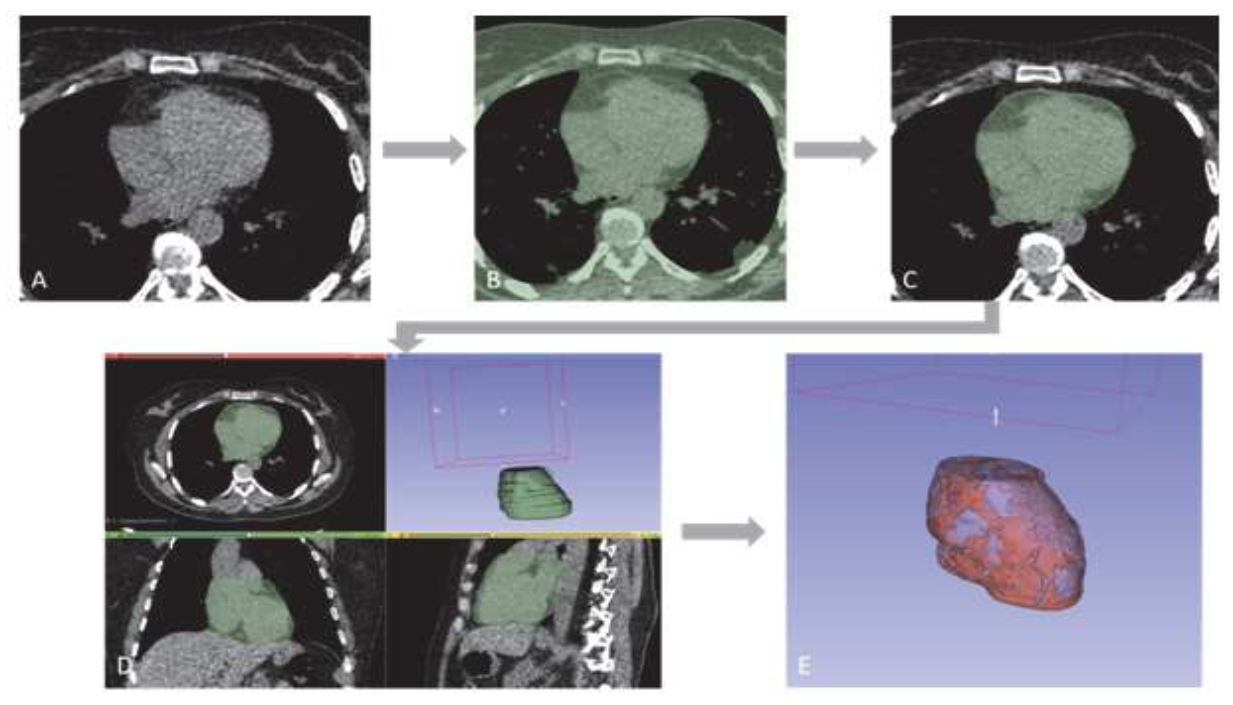

2.3. EAT Segmentation Model

2.3.1. Manual Segmentation

2.3.2. Manual Segmentation and Slice Detection Model